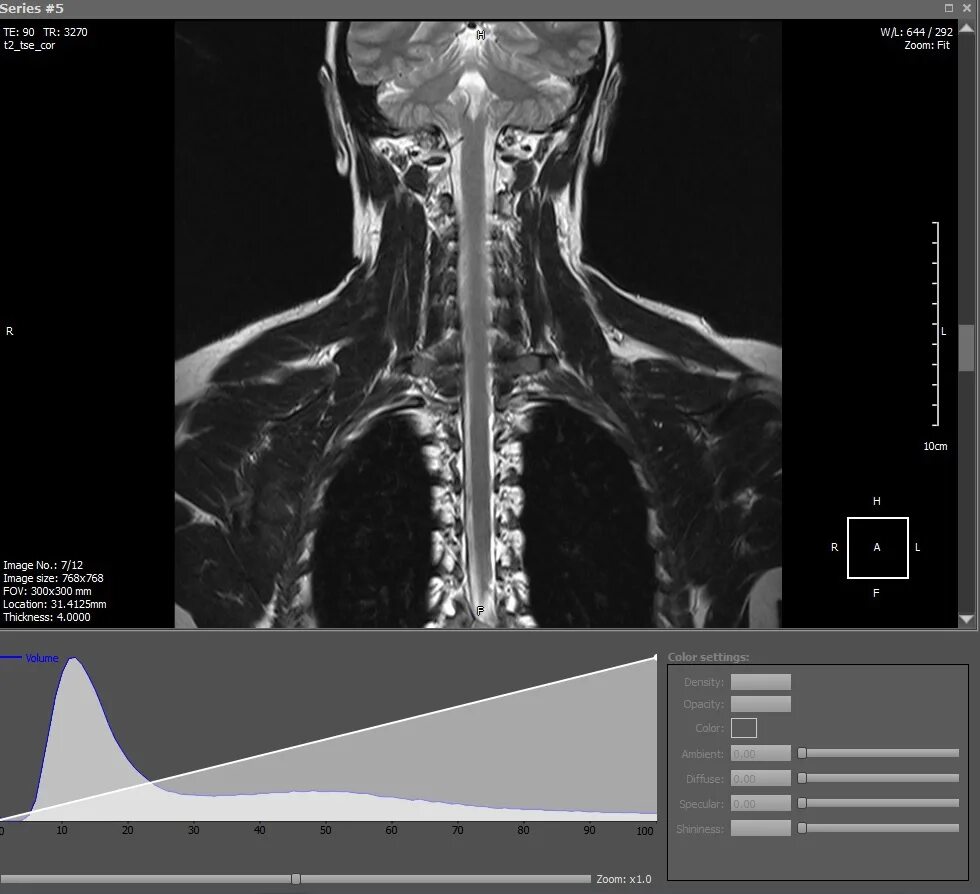

Dicomdir чем открыть снимки мрт